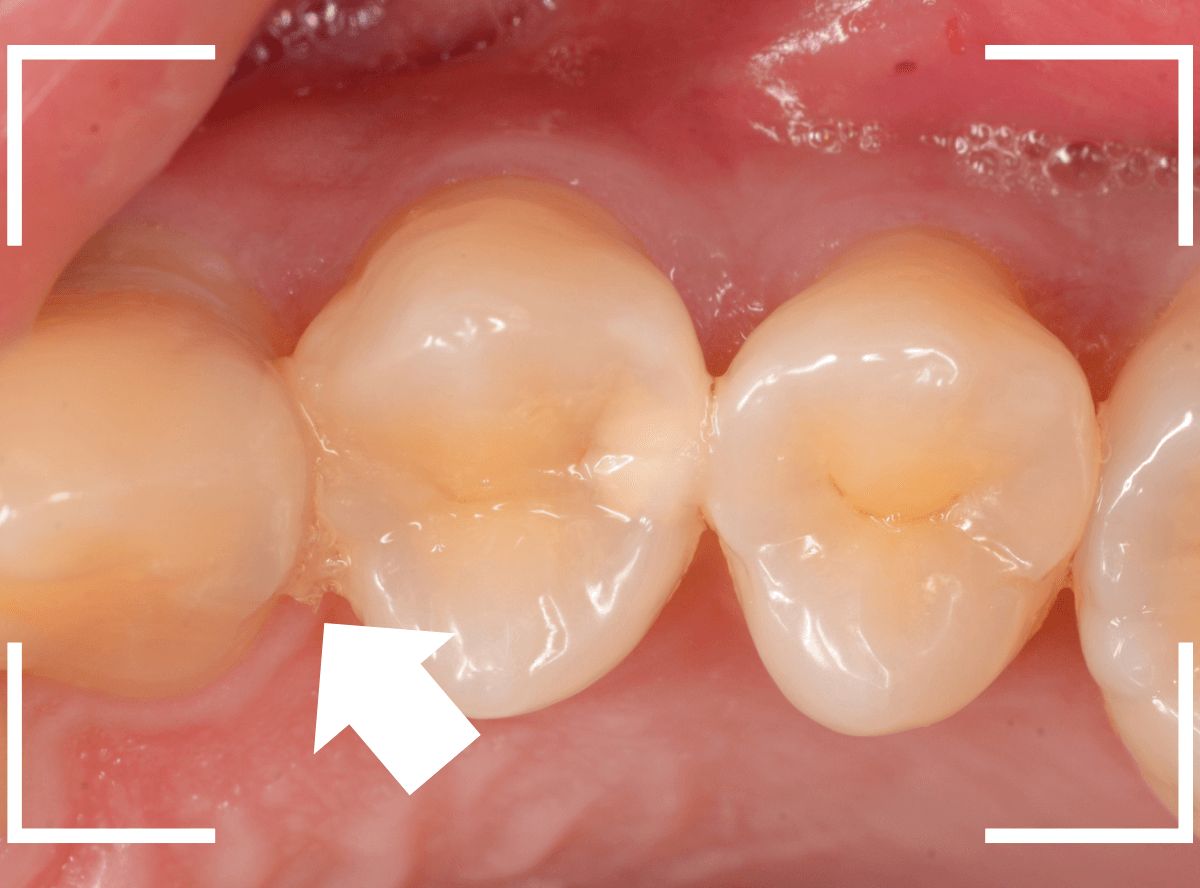

Case.1 奥歯のスキマが大きな虫歯!

他の歯の治療目的で来院された患者さんです。

全体検査の際、ちょっとこの歯、アヤシイなと思いましたが、確証はありませんでした。

(この写真で改めて見ると、かなりアヤシイと思いました)

レントゲン写真で確認すると、かなり大きな虫歯でした。

しばらく経過観察した後、特に症状がありませんでしたので、隣の歯をレジンで治療後、ジルコニア・インレー(70,000円(税込み/2024年1月現在))で治療することにありました。

治療後の写真です。

特に症状もなく、審美性も高く治療することができました♪